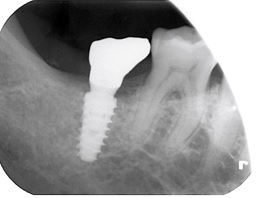

インプラント症例(60代以上、術後)下顎左側にインプラントと補綴装着後のレントゲン

欠損部位に対応する対顎の歯が挺出(伸長)しており、噛み合わせのスペースが限られている状態でした。

この状態では、一般的な補綴設計が難しく、治療方針の検討が必要なケースでした。

そのため、噛み合わせのバランスを優先し、補綴物の高さを調整する設計としています。

対顎歯の伸長がある症例では、理想的な高さでの補綴が難しい場合があります。

本症例では、削合によるリスクを避けるため、噛み合わせの安定を優先した治療を行いました。